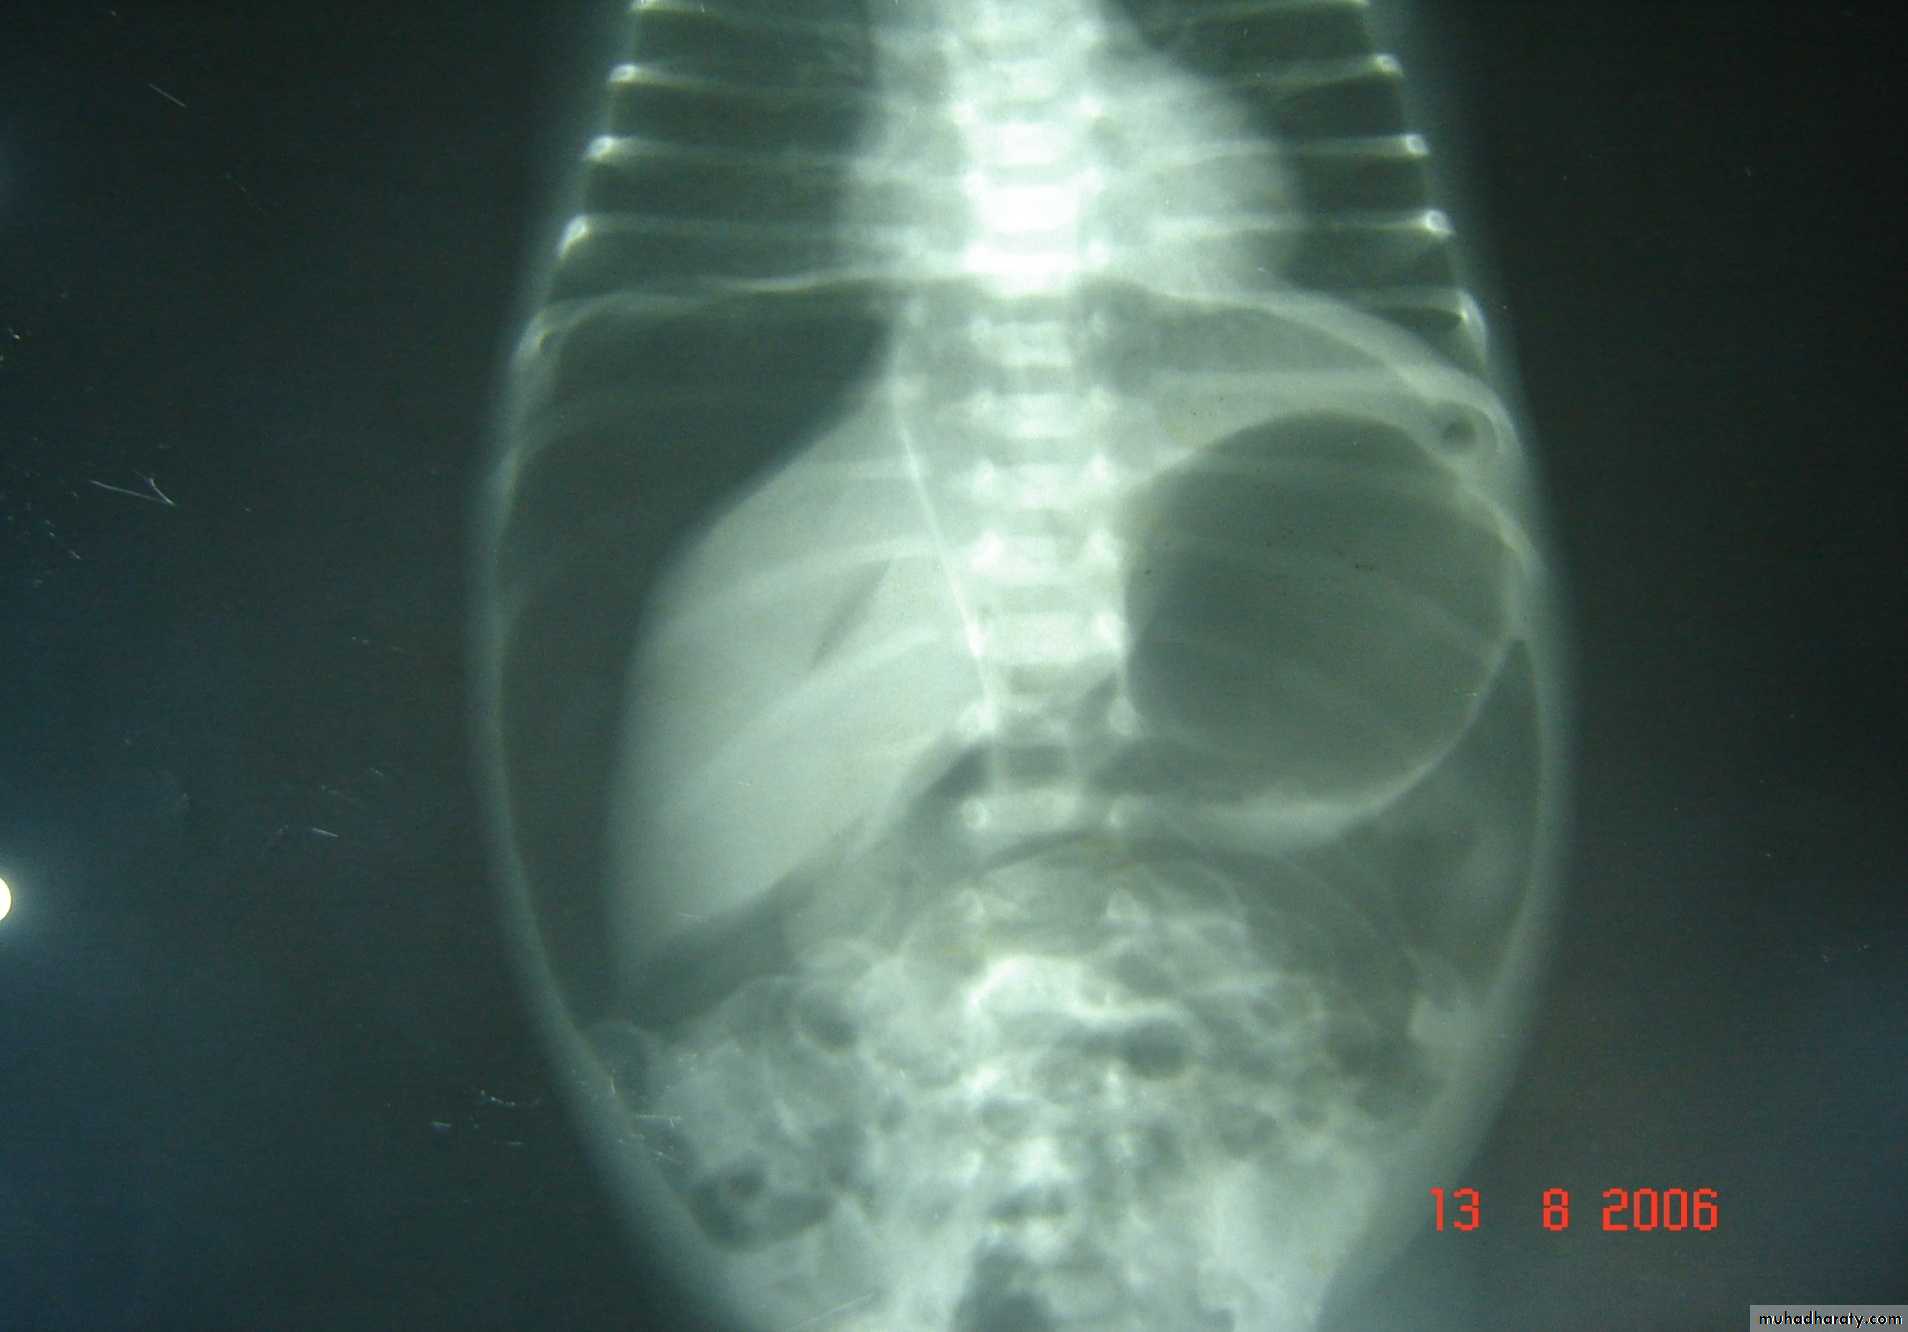

Necrotizing enterocolitis(NEC):

gastric retention (frequently bilious), distention & occult or bright red bd in stool, should raise concern. Although this disease usually occurs in premature infants, it also may occur in full-term infants.

Abdominal XR: pneumatosis intestinalis, gas in the portal vein, or free intraperitoneal gas(pneumoperitoneum) supports Dx.

g.i.t 1

pneumoperitoneum